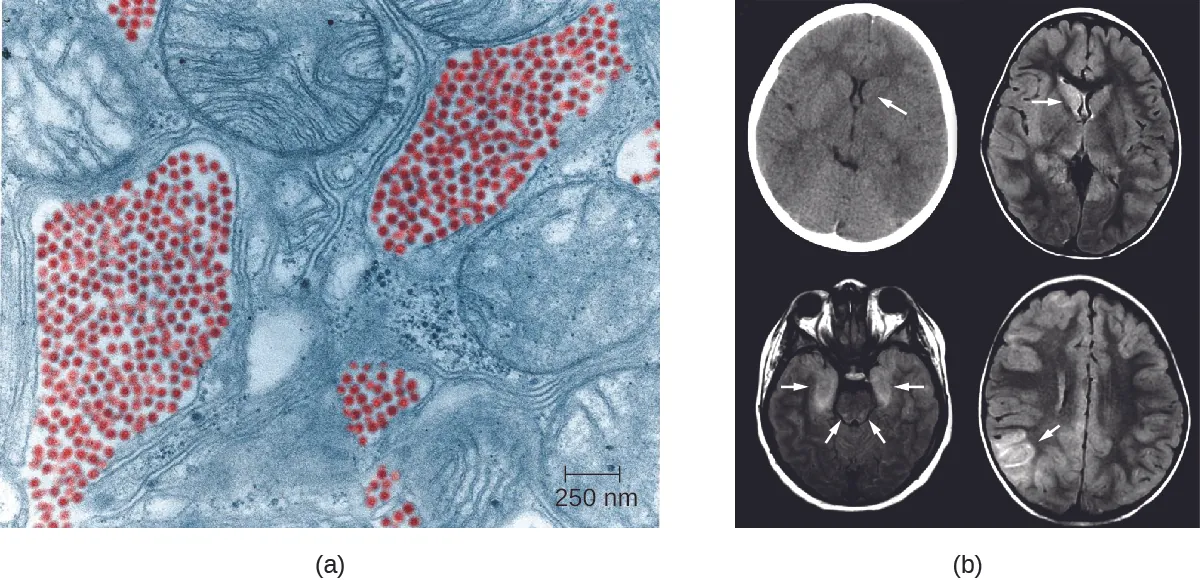

Eastern equine encephalitis (EEE) is caused by eastern equine encephalitis virus (EEEV), which can cause severe disease in horses and humans. Birds are reservoirs for EEEV with accidental transmission to horses and humans by Aedes, Coquillettidia, and Culex species of mosquitoes. Neither horses nor humans serve as reservoirs. EEE is most common in US Gulf Coast and Atlantic states. EEE is one of the more severe mosquito-transmitted diseases in the United States, but fortunately, it is a very rare disease in the United States (Figure 26.13).1920

a) electron micrograph showing small red dots next to larger cellular structures. B) brain scans with arrows pointing to dark regions in the brain.

Figure 26.13 (a) A false color TEM of a mosquito salivary gland cell shows an infection of the eastern equine encephalitis virus (red). (b) CT (left) and MRI (right) scans of the brains of children with eastern equine encephalitis infections, showing abnormalities (arrows) resulting from the infection. (credit a, b: modifications of work by the Centers for Disease Control and Prevention)